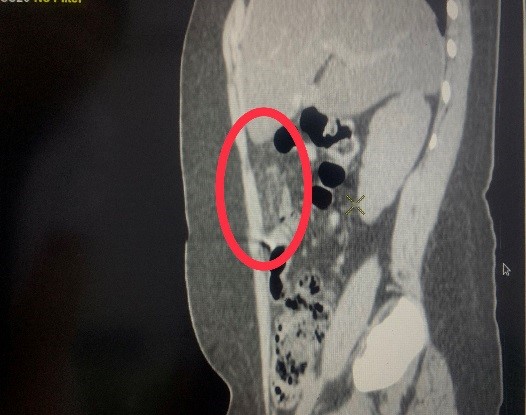

Hình 1,2,3: Hình ảnh theo dõi xoắn mạc nối trên phim chụp CT ổ bụng

khác. Sau đó trẻ được chụp CT ổ bụng để chẩn đoán. Với kết quả ruột thừa bình

thường nhưng có đám viêm nhiễm vùng mạn sườn phải, trẻ đã được các bác sĩ khoa

Ngoại tổng hợp chẩn đoán Xoắn mạc nối lớn và chỉ định mổ cấp cứu bằng phương